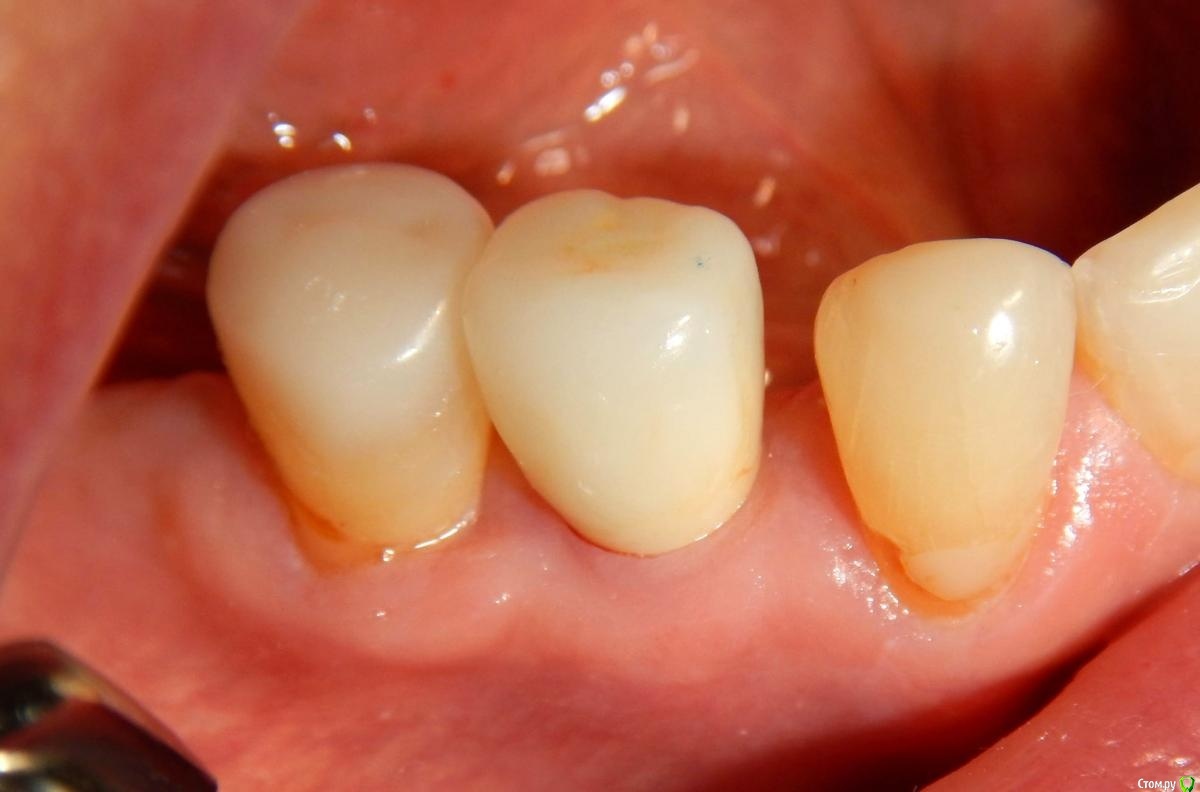

Astronaft Опубликовано 24 января, 2021 Поделиться Опубликовано 24 января, 2021 (изменено) Одиночный цирнокиевый имплантат и расщепление без графта. Пациентка:тонкая хрупкая женщина 55 лет, сконцентрированная на своем здоровье, в некоторой мере мнительная.всегда тяжелые заживления после удалений (по опросам)есть результаты Клиффорд теста (такая книжка под 200 страниц с in vitro аллерго-пробами на все известные материалы) Поставленная цель:только цирконий Мне было интересно найти вариант найболее приемленый пациентке и мне. С минимом хирургического риска и риском сожаления пациентки про выбор костного материала. Во-первых, я не использую аллографты - философски, чужие протеины, неприятный запах - просто основываясь на своем мнении.Во-вторых, мнительные пациенты склонны "пойти и почитать" до или потом и как следствие внушить себе вещи которых может и не было. Но по скольку мысль материальна... Все обсудил заранее.План: ридж сплит (расщепление), имплантат без графта, свободный СТ графт; если случается вестибулярная рецессия - пилим зирконий во рту. Ридж сплит сделан пьезотомом - крестальный и вертикальные пропилы на глубины около 8-10мм.Пилотное сверло.Развдвинул кость остеотомами от 1.6мм до 3.5мм в диаметре.Очень мягкая кость - напомнила мегкую максиллу плотности ногтевой пластинки вестибулярно.Имплант встал легко, но торк 40нсм. СТ графт из области 18. Деэпителизирую скальпелем уже потом. Тут интересно отметить, что я перестал боятся ошметков эпителия.Пончо сверху имплантата (а-ля шашлык Карлоса).Швы. PTFE всегда хорош. 12 недель.Красивая десна.Периотест -5.8 - отличный результат.Оттиск. Циркониевая коронка симметричная другой стороне. Изменено 24 января, 2021 пользователем Astronaft 19 Ссылка на комментарий

Astronaft Опубликовано 25 января, 2021 Автор Поделиться Опубликовано 25 января, 2021 Спасибо.День операции, 12 недель, день цементировки. 3 1 Ссылка на комментарий